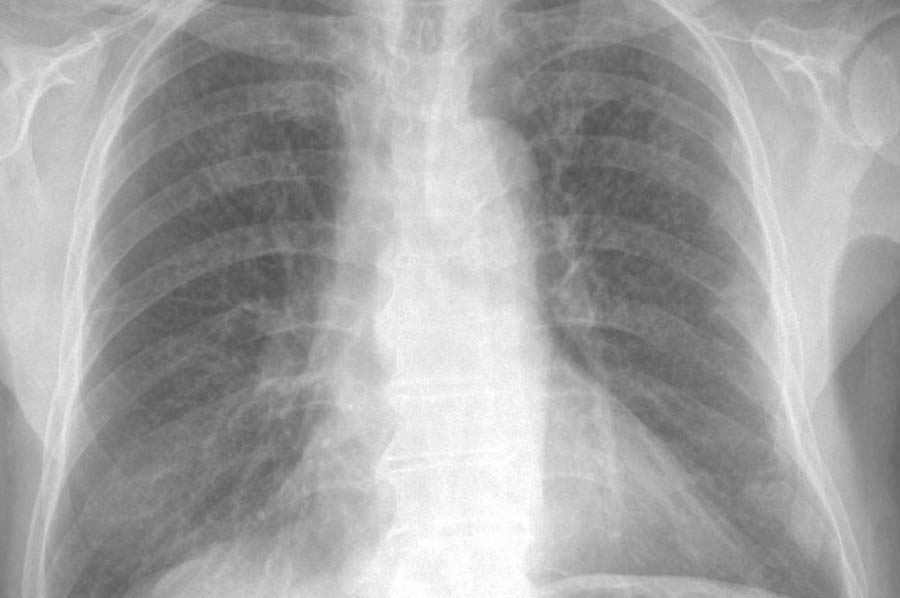

tuberkulose 1"From a purely morphological point of view, it is likely that the dimples and indentations found on the inside of the anterior skull are the remains of a meningitis caused by tuberculosis," Prof. Schulz explained in an interview.

Prof. Schulz and his US colleague and researcher John Kappelmann from the University of Austin discovered the indentations in the skull parts, which were around one to two millimeters in size, when they were researching the skull parts. In their view, both the shape and the placement of the indentations clearly indicate inflammation of the meninges. These signs are characteristic of a certain form of tuberculosis, leptomeningitis tuberculosa, which can only develop in people who are still alive.